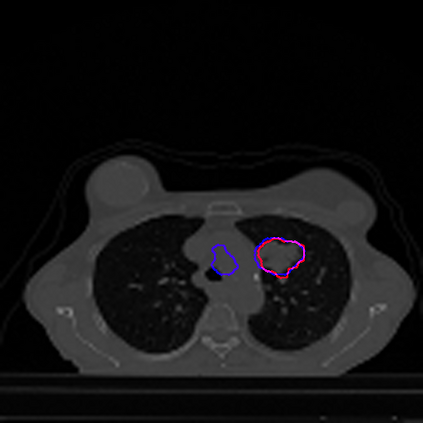

Lung cancer is a leading cause of death in most countries of the world. Since prompt diagnosis of tumors can allow oncologists to discern their nature, type and the mode of treatment, tumor detection and segmentation from CT Scan images is a crucial field of study worldwide. This paper approaches lung tumor segmentation by applying two-dimensional discrete wavelet transform (DWT) on the LOTUS dataset for more meticulous texture analysis whilst integrating information from neighboring CT slices before feeding them to a Deeply Supervised MultiResUNet model. Variations in learning rates, decay and optimization algorithms while training the network have led to different dice co-efficients, the detailed statistics of which have been included in this paper. We also discuss the challenges in this dataset and how we opted to overcome them. In essence, this study aims to maximize the success rate of predicting tumor regions from two dimensional CT Scan slices by experimenting with a number of adequate networks, resulting in a dice co-efficient of 0.8472.